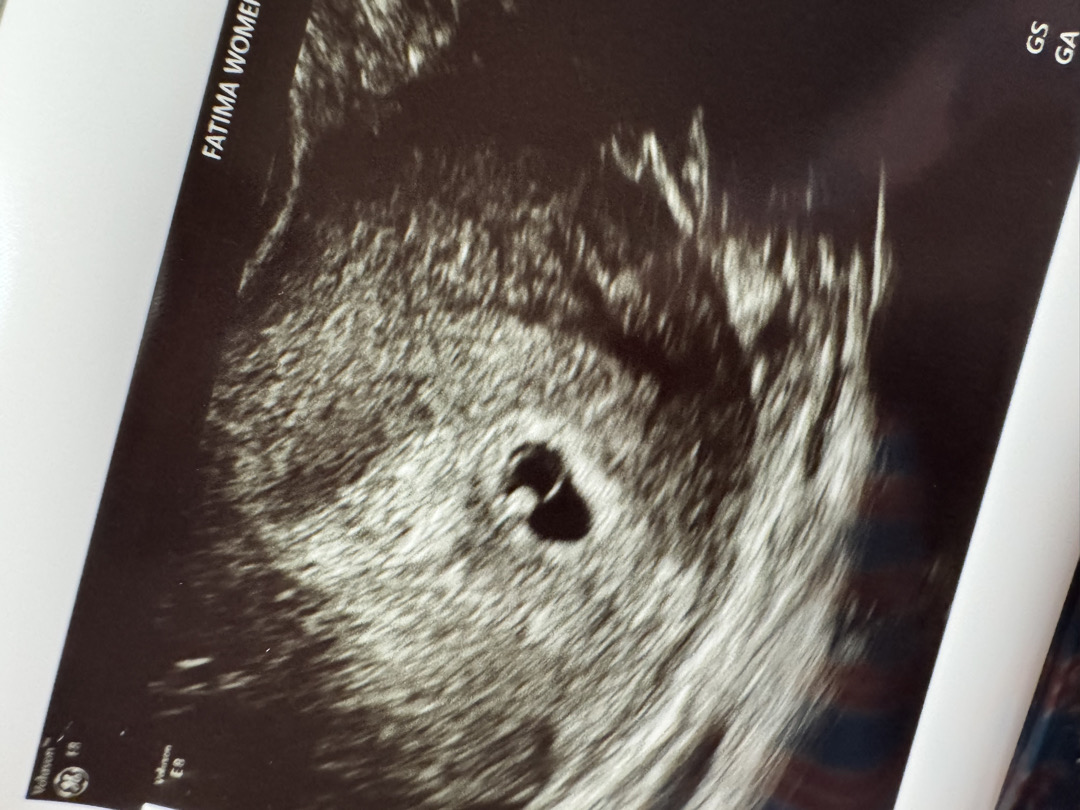

막생 5월 8일/ 네이버 주수 5주 4일/ 초음파에는 5주 0일로 찍히더라구요 💛 아기집, 난황, 심장 깜빡임(소리x)까지 봤는데 괜찮아 보이나요? 의사선생님은 2주 뒤에 보자고만 하셔서,,, ㅋㅋㅋㅋㅋㅋㅋㅋㅋ